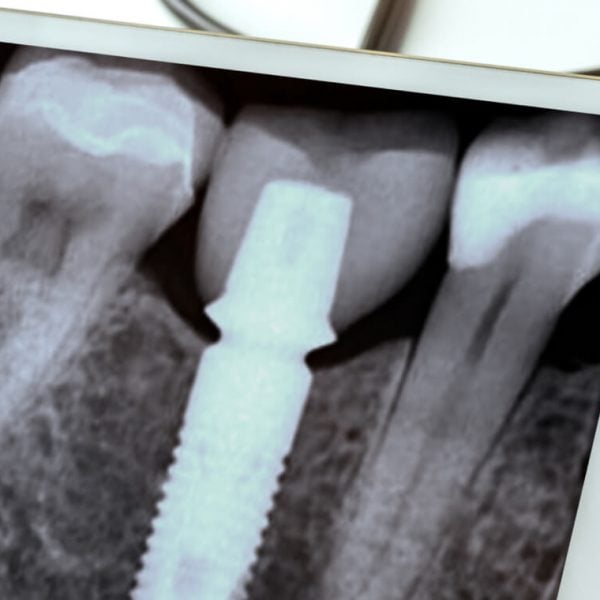

Dr. Ye specializes in full-mouth rehabilitation and can restore your smile back to its natural beauty and optimal oral health. With a variety of superior services and cutting-edge technology, our experienced team can help you achieve your desired smile.

From minor restorative services to complex, full-mouth rehabilitation, Dr. Ye welcomes each and every patient no matter their needs. We’ll work together to provide you with the highest quality of care and long-lasting, exceptional results.